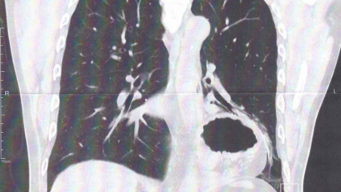

食道裂孔ヘルニア

食道裂孔ヘルニアってどんな病気なの?手術体験記